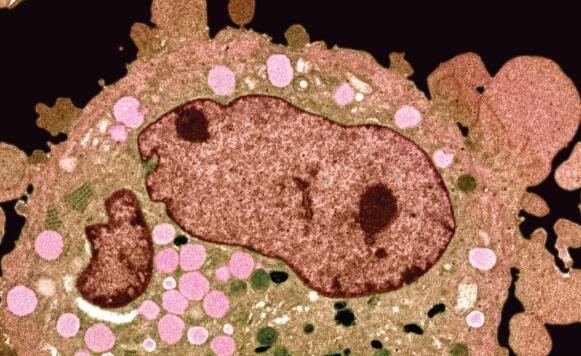

圖片來源:2016.igem.org